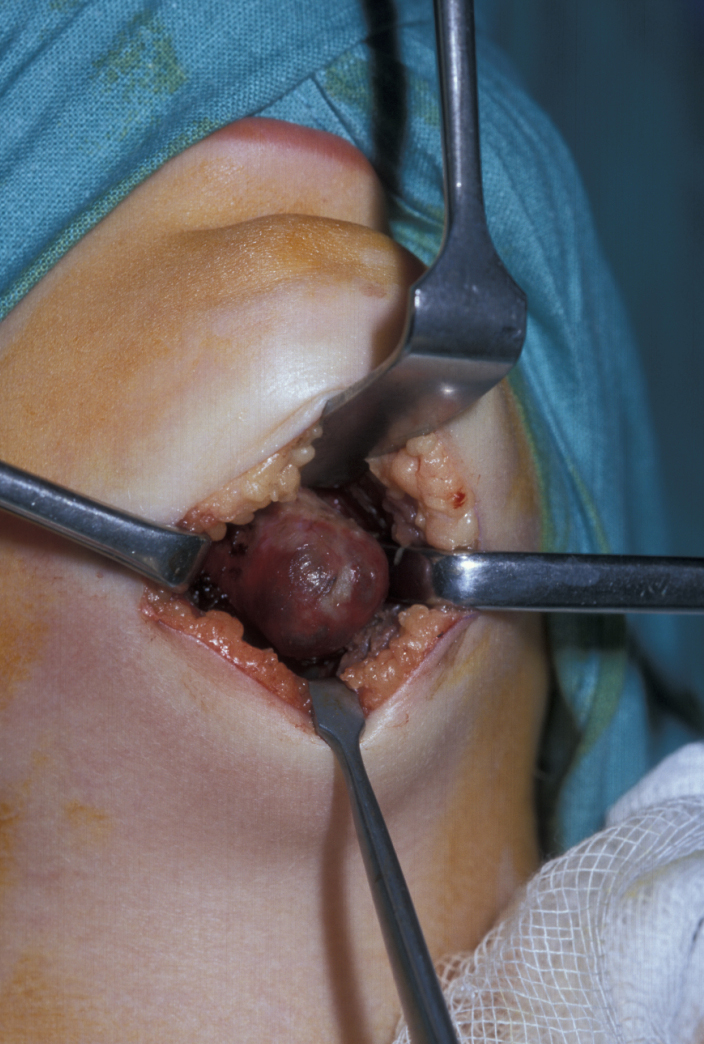

Figure 16 illustrates the distortion of the sternomastoid muscle by a branchial cyst, Figure 17 shows a branchial cyst being removed from beneath the sternomastoid muscle.

Figure 16: Skin flap elevated to show the distortion of sternomastoid caused by a branchial cyst and the preserved great auricular nerve.

Figure 17: The dissected branchial cyst being removed from beneath the sternomastoid